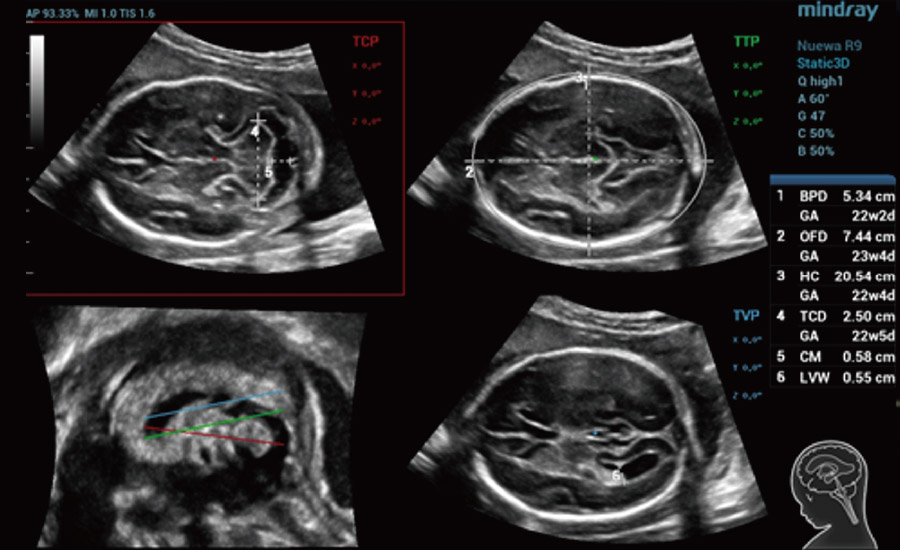

Scenario-oriented Full-stack Intelligence

Combining advanced algorithms and domain-specific knowledge, the innovative Smart Scene solution enables auto identification of tissue characteristics and provides organ-specific diagnosis with full-stack intelligence. Based on auto scenario identification, the solution not only realizes smart 2D scanning with auto settings and measurements, but also delivers 3D full-stack intelligence in every step from volume imaging optimization to the difficult 2D plane acquisition, and quantification throughout whole procedure. It helps a lot in reducing the dependency on clinical skills, while increasing diagnostic accuracy, confidence and efficiency.

Obstetrics